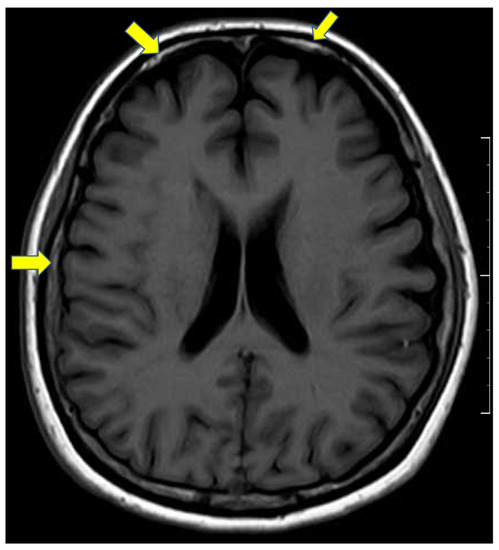

2. Case Presentation